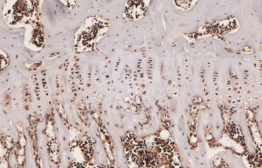

NR4A2 protein distribution in cartilage from the DMM model of arthritis.

Research led by Dr. Kim Mix aims to elucidate the molecular and cellular events driving cartilage degradation and synovial inflammation in arthritis. The primary goal of this research is to identify novel molecular mechanisms that could be targeted to block inflammation and stop the progression of arthritis. To this end, the lab is investigating an orphan nuclear receptor overexpressed in arthritic tissues, nuclear receptor 4A2 (NR4A2 / Nurr1). This transcription factor regulates the expression of genes mediating inflammation and cartilage degradation in arthritis. Targeting NR4A2 may provide a novel strategy to alleviate symptoms of arthritis and preserve joint function.